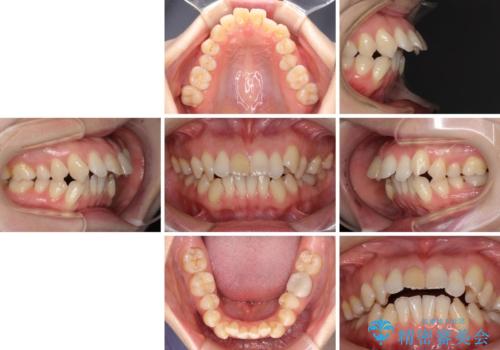

- 上の前歯の飛び出した感じを改善したいとのことで来院された患者様です。

上顎左右第一小臼歯2本、下顎左右第二小臼歯2本を抜歯し、ワイヤー装置にて口元を引っ込めるよう矯正治療を行うこととしました。

上下の前歯に隙間が空くほど上顎前歯が前に飛び出していましたが、抜歯矯正により上下前歯がぴったりと付くほど口元を引っ込めることができました。